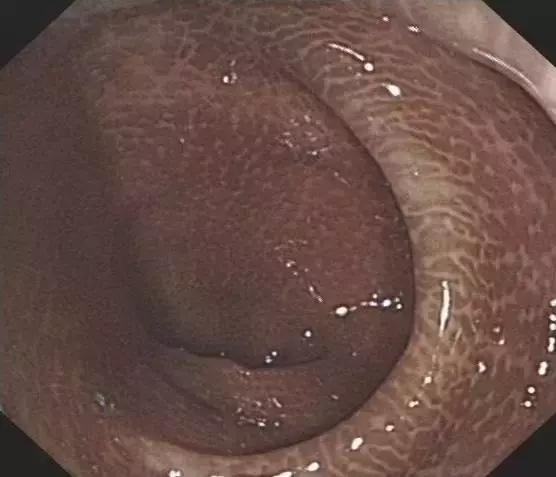

而长期使用这类刺激*药性**物,不仅会对药物形成依赖,还会对肠道的蠕动及分泌功能有所损伤,导致结肠黑变病,久而久之甚至引起癌变。

▲黑变病结肠

然而,结肠黑变病还不是最可怕的,最可怕的是滥用泻剂针对肠功能和肠动力的损害,这些是不可逆的!